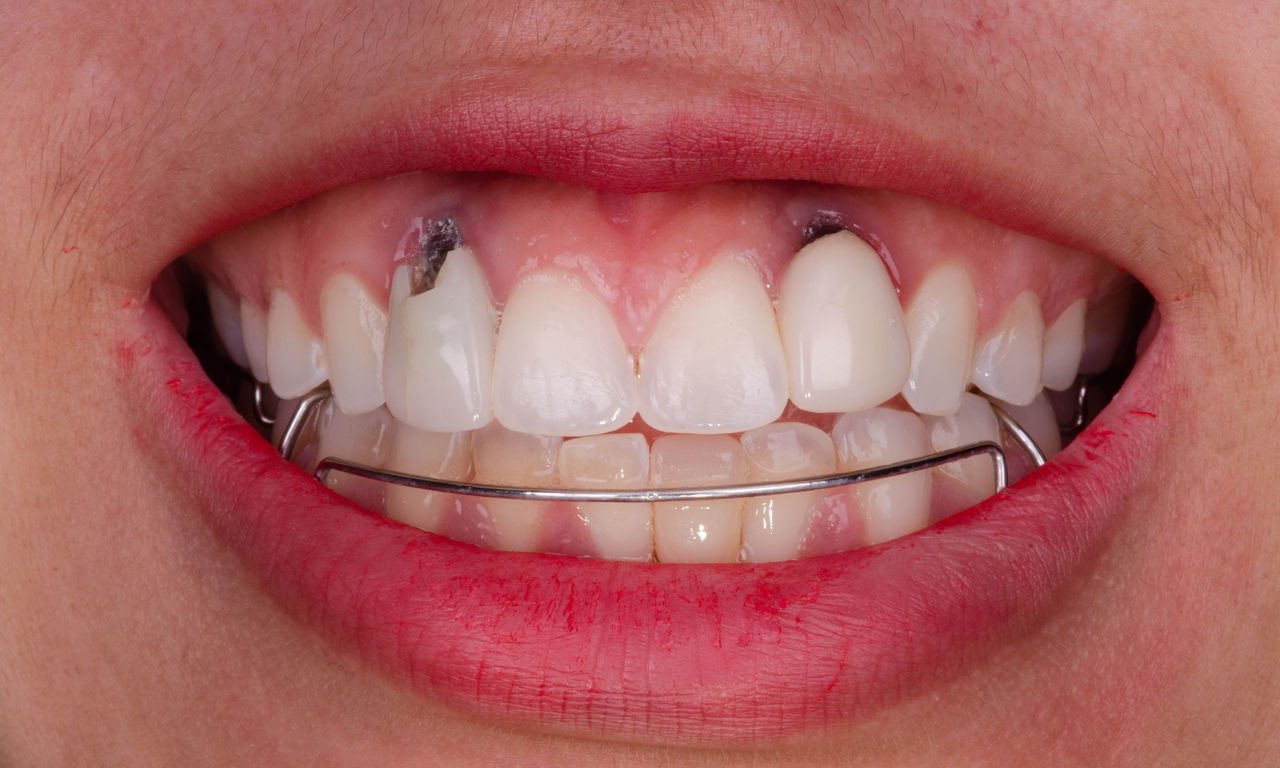

Before

Inadequate fillings on teeth 12-22, an uneven gingival line on 12 and 11 and incisal edges severely eroded.

After

Four highly esthetic and individualized lithium disilicate ceramic crowns.